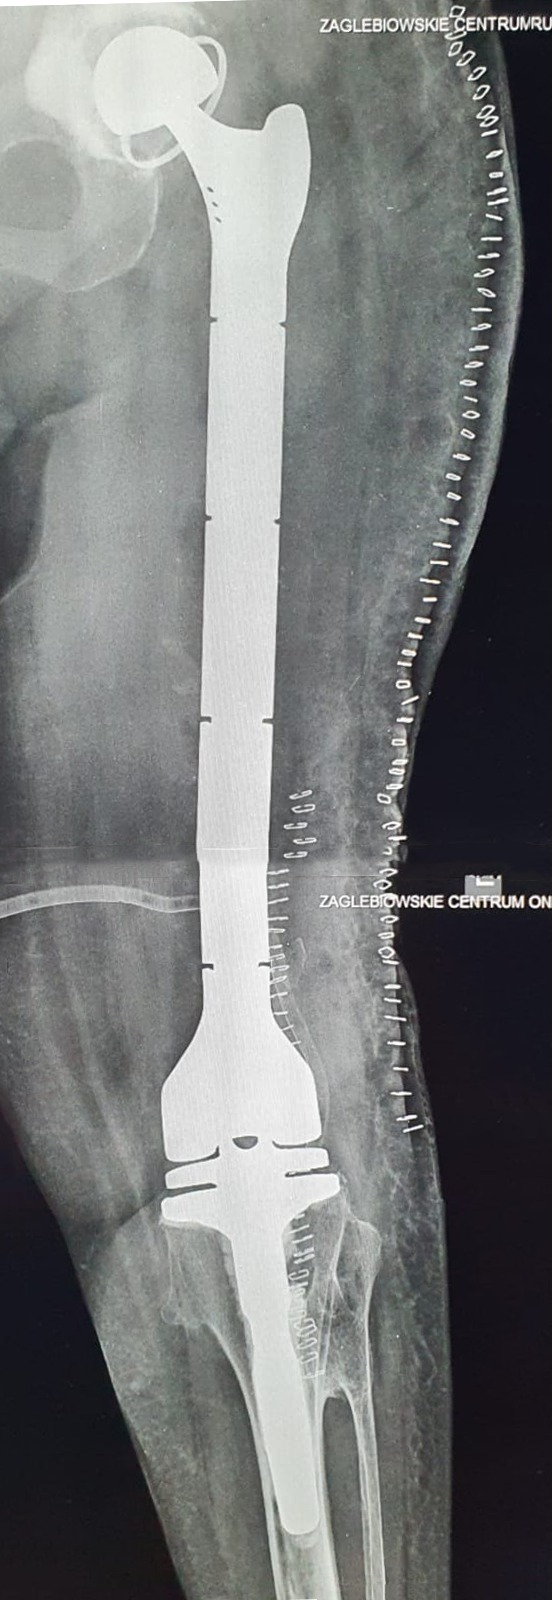

Nowoczesna operacja całkowitej wymiany stawu biodrowego połączonego elementem udowym z endoprotezą stawu kolanowego tzw. „total femur” została przeprowadzona w Zagłębiowskim Centrum Onkologii. Zespół Oddziału Chirurgii Ortopedycznej, Onkologicznej i Rekonstrukcyjnej zrealizował zabieg pod koniec 2021 r., dając 74-letniej Pacjentce drugą szansę na samodzielne poruszanie się.

W Oddziale Ortopedii dąbrowskiego szpitala przeprowadzono operację wymiany stawu biodrowego połączonego elementem udowym z endoprotezą stawu kolanowego. Była to pierwsza w placówce operacja tego typu, do której wskazaniem było niepowodzenie leczenia wieloodłamowego złamania osteoporotycznej kości udowej. Wcześniej podobne zabiegi wykonywane były w mniejszym zakresie – endoprotezoplastyka poresekcyjna stawu biodrowego lub kolanowego. Ta innowacyjna operacja rozpoczęła jednak możliwość przeprowadzenia tego typu zabiegów, przywracających zdolność samodzielnego ruchu chorym onkologicznym oraz Pacjentom w podobnych, trudnych przypadkach.

Zabieg wykonany przez zespół chirurgów z Zagłębiowskiego Centrum Onkologii polegał na usunięciu endoprotezy stawu biodrowego i kości udowej, a następnie zaimplantowaniu w to miejsce tzw. „total femur”, czyli endoprotezy stawu biodrowego połączonego elementem udowym z endoprotezą stawu kolanowego. Operacja przeprowadzona została na 74-letniej Pacjentce, pierwotnie leczonej z powodu złamania szyjki kości udowej, do którego doszło w 2020 roku. Wówczas wykonana została endoprotezoplastyka stawu biodrowego. Z uwagi jednak na ponowny uraz i złamanie wielofragmentowe dalszej części kości udowej, ortopedzi wykonali zespolenie trzonu kości udowej, które na dalszym etapie uległo kilkakrotnie destabilizacji. Równocześnie nie uzyskano pożądanego zrostu złamania. Biorąc pod uwagę rozległe ubytki kości, implant endoprotezy stawu biodrowego, osteoporozę oraz trudności w uzyskaniu prawidłowego zrostu, nie można było wykonać kolejnej operacji rekonstrukcyjnej kości udowej, dlatego lekarze zadecydowali o zastosowaniu nowej metody operacyjnej, czyli całkowitej wymianie kości udowej.

Dzięki zabiegowi Pacjentka odzyskała możliwość poruszania się. Proces leczenia rozpoczął się jeszcze w 2020 roku, od naprawy złamania szyjki kości udowej. Był on długi i momentami bolesny, jednak dzięki zastosowaniu radykalnego rozwiązania w postaci implantu modularnej protezy poresekcyjnej, składającej się z endoprotezy stawu biodrowego, elementu udowego oraz endoprotezy stawu kolanowego, chora porusza się z pełnym obciążeniem operowanej kończyny już od drugiej doby po zabiegu”